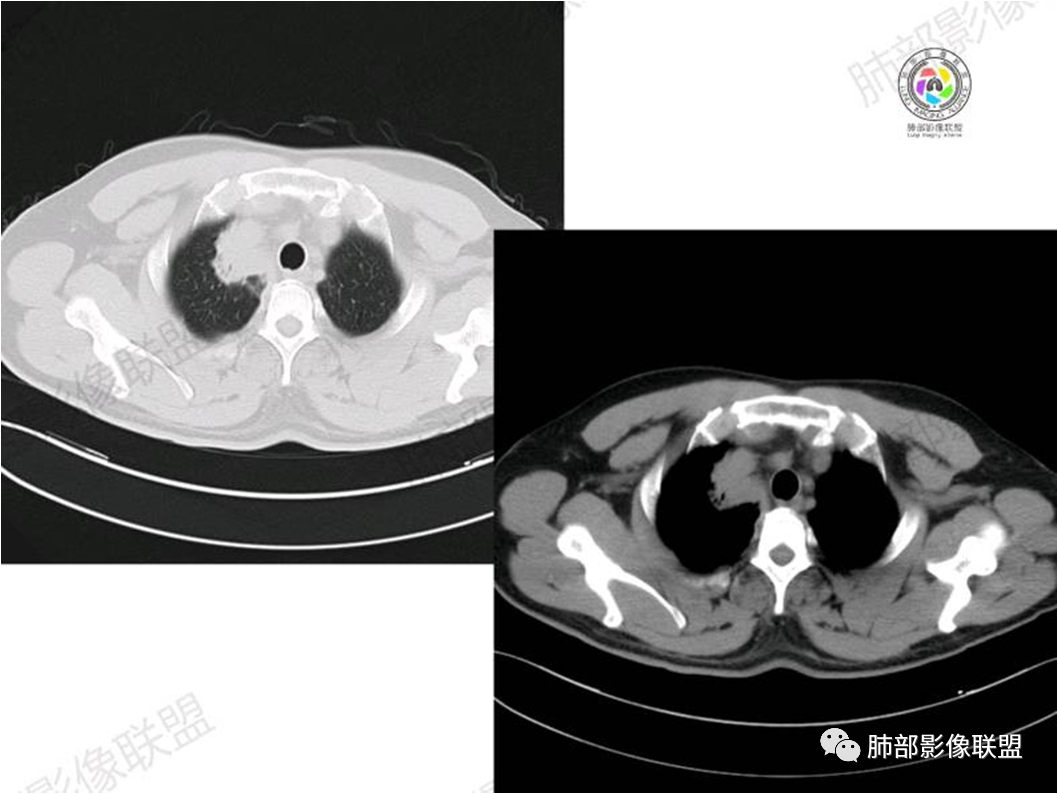

胸部CT:

中年男性,偶有咳嗽,右肺上叶近纵膈旁占位,内可见僵硬的支气管和小空泡征,病灶边缘可见分叶,毛刺,增强病灶中度以上不均匀强化,可见血管造影征,考虑恶性病变,腺癌可能性大。

中年男性,右肺上叶尖段团片病灶,密度均匀,内部支气管充气相,渐进狭窄,强化均匀,血管造影,纵隔侧未见侵犯,诊断:良性,慢性非特异性炎症/机化性炎症,IMT

右肺上叶纵隔胸膜侧一实性肿块,与纵隔胸膜宽基底相连,局部脂肪间隙消失,形态欠规则,内部可见多个小空泡,平扫密度尚均匀,增强后可见点条状强化,内部穿行血管,周围肺组织干净,纵隔淋巴结略肿大,男性44岁,只有咳嗽,考虑恶性肿瘤,腺癌,鳞癌。鉴别结核,OP,炎性假瘤。

患者中年男性,咳嗽就诊,无其他不适。胸部CT:右肺上叶尖段上纵膈旁肿块,边界清楚,边缘光滑,内见支气管受压变窄,伴阻塞性改变,增强均匀强化,见血管造影征。综合考虑恶性病变,小细胞肺癌或淋巴瘤。气管镜活检应能明确。

MALT淋巴瘤影像表现为实变、结节及磨玻璃影,其中实变是其特点,胸膜下或支气管血管束节段性分布具有特征性,跨叶征较常见,这可能与肿瘤细胞进入血循环后往往又回到上皮黏膜部位,它们从一处黏膜到另一处黏膜,但不会到外周淋巴组织等有关。国外多名学者的影像-病理研究报道认为其病理学基础是由于肿瘤细胞沿支气管血管束周围间质及胸膜浸润生长,形成小叶间隔增厚、支气管血管束增粗等间质性改变,进一步浸润肺泡壁、充填肺泡腔。

①实变的出现率100%,多表现为两(89%)或单肺多发,密度均匀,与邻近胸壁肌肉的密度大致相等,少见钙化(15%),这与病灶内血管保持 完整,血供丰富,且肿瘤生长缓慢,对缺氧耐受好,不易坏死有关。边缘磨玻璃影或晕征具有特异性,其病理学基础是肿瘤细胞对小叶间隔、肺泡壁的淋巴瘤样浸润;

③扩张的充气支气管为其较特征性的表现,出现率约为89%,支气管管壁无破坏,支气管常扩张并达病灶的边缘,这与炎症性肺癌明显不同,其病理学基础是肿瘤起源于肺间质,肿瘤细胞沿着脏器解剖结构生长,周围增生的结缔组织牵拉导致支气管扩张,因而这类支气管扩张在肿瘤治疗后有时可消失;

④血管造影征是另一 点,强化的肺血管形态及走行正常,无扭曲或增 粗,其病理学基础为肿瘤细胞沿间质增生浸润,不破坏血管或支气管,病灶内肺支架结构完整,本研究发现率为75%;